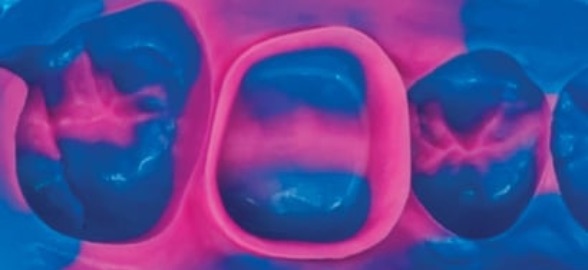

La adhesión en odontología ha permitido mejorar de forma considerable los procedimientos clínicos restauradores.

En este blog te presentaremos un caso práctico de estratificación en una restauración clase IV con composite realizada con G-aenial A’CHORD.

La práctica hace al maestro y en la toma de una impresión dental esta no es la excepción.